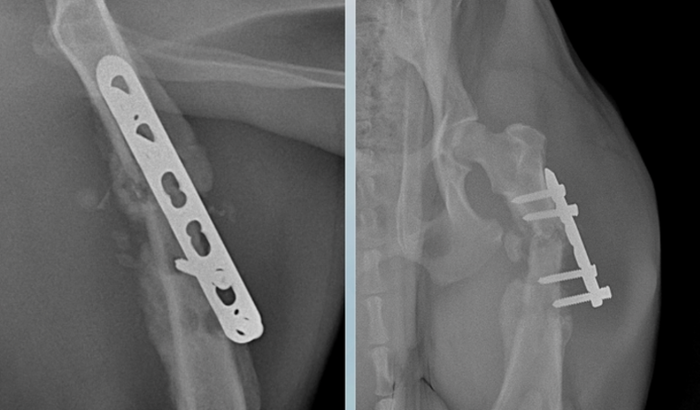

Ele faturou o fêmur, e teve uma luxação na pata da frente, teve que passar por uma cirurgia na clínica vida animal, foi colocado placa no fêmur, na pata da frente gesso, aonde meu gasto foi de 5.000,00, com a cirurgia fêmur e tentativas de tala na pata da frente que não deu certo e por fim o gesso.

Com passar dos dias notei que começou mancar, levei novamente repetir raio-x, e a placa fez uma nova fratura no local do parafuso, segundo os veterinários excesso de movimentos , mesmo com todo cuidado que tive em manter ele mais preso para recuperação, infelizmente eles não entendem que não pode força, voltou a sentir dor. Está sendo medicado.

E agora precisa passar por uma nova cirurgia, da qual eu não tenho mais condições de pagar, Valor da cirurgia 3.415,00 , aonde Será tirado a placa e usado outra técnica na fratura e 20 dias de internamento para evitar se movimentar muito, e ter uma boa recuperação.